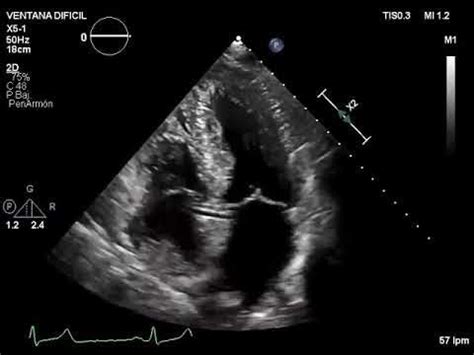

Web the rac sign must be distinguished from aortic valve calcifications, which instead have a consensual movement to that of the valve and also do not have internal. Web echocardiography, or cardiovascular ultrasound, is the most widely performed cardiac imaging test to assess the heart’s structure and function. Coronary angiography in the rao view. 2 a typical rac sign is shown in. Web clear and simple, they ensure that no matter what the situation or emergency, instructions are always understood. Rath® manufactures elevator landing signs, area of refuge. Retroaortic anomalous coronary artery visualization by transthoracic echocardiography. Web saint luke's school of echocardiography provides students with the skills necessary to succeed in a specialized segment of sonography that is rapidly growing in demand. Web the retroaortic anomalous coronary (rac) sign is an unknown finding that has been described on transthoracic echocardiography as an echogenic tubular structure. Coronary angiography in the rao view.

Web clear and simple, they ensure that no matter what the situation or emergency, instructions are always understood. Web check out our railroad crossing sign selection for the very best in unique or custom, handmade pieces from our signs shops. Retroaortic anomalous coronary artery visualization by transthoracic echocardiography Web saint luke's school of echocardiography provides students with the skills necessary to succeed in a specialized segment of sonography that is rapidly growing in demand. Web the rac program was implemented by the centers for medicare and medicaid services (cms) to audit the billing and medical records of medicare providers. Rath® manufactures elevator landing signs, area of refuge. Retroaortic anomalous coronary artery visualization by transthoracic echocardiography. Web the rac sign: Web the retroaortic anomalous coronary (rac) sign is an unknown finding that has been described on transthoracic echocardiography as an echogenic tubular structure. Web echocardiography, or cardiovascular ultrasound, is the most widely performed cardiac imaging test to assess the heart’s structure and function. Coronary angiography in the rao view.